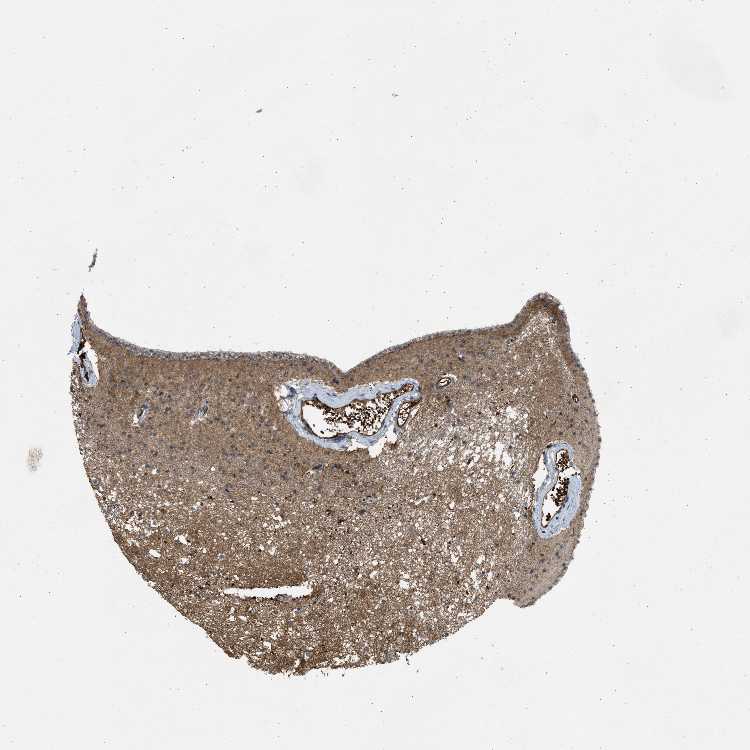

CAUDATE - Antibody stainingi

Antibody staining in the annotated cell types in the current human tissue is reported as not detected, low, medium, or high, based on conventional immunohistochemistry profiling in selected tissues. This score is based on the combination of the staining intensity and fraction of stained cells.

Each image is clickable and will lead to virtual microscopy that enables deeper exploration of all samples and also displays staining intensity scores, fraction scores and subcellular localization as well as patient and tissue information for each sample.

Antibody CAB018561

Glial cells Medium

Neuronal cells Medium